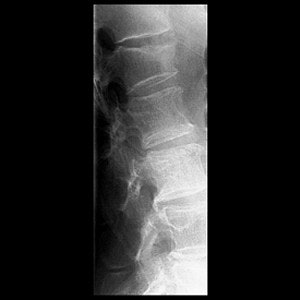

| Final result of a vertebroplasty procedure on a lateral radiograph. Image courtesy of Dr. John Mathis. |